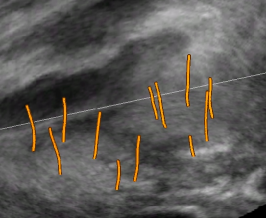

The framework was validated on 278 registrations of 295 US volumes from 17 patients. The 17 reference images were acquired shortly before the intervention, and the tracking images were acquired after a biopsy shot. The clinical protocol was approved by the ethical committee of the XXX hospital, Town, Country, and all patients consented to participate to the study. The images were acquired with a GE Voluson and a RIC5-9 endorectal US probe. The algorithms were executed on a 4-core 2.6Ghz processor. In order to provide a reference gold standard for the evaluation of registration accuracy, experts manually segmented 467 point fiducials that were clearly identifiable on multiple images (e.g. calcifications and cysts). The distances between fiducial pairs were measured after registration to estimate the local accuracy. Note that the unavoidable segmentation error increases the measured error in average; this approach hence underestimates accuracy. Accuracy was computed for all registrations that were qualified as valid by experts after visual inspection, which represent 97,8 of the registrations. The results for both rigid and elastic registration are given in Tab. 1, and a visual illustration of the registration performance is given in Fig. 2. Fig. 3 shows 3D biopsy maps created with our biopsy tracking system.